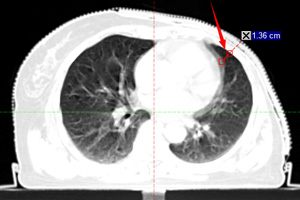

瓦里安最新的呼吸门控系统(Respiratory Gating for Scanners, RGSC),通过红外反射采集患者的呼吸波形曲线,然后将呼吸信息传输到计算机断层成像(Computed Tomography,CT)系统并自动同步到该患者的放射治疗计划程序,在完成计划设计后,只需要在治疗准备界面应用上RGSC记录下来的患者呼吸曲线即可使用TrueBeam直线加速器进行呼吸门控治疗。